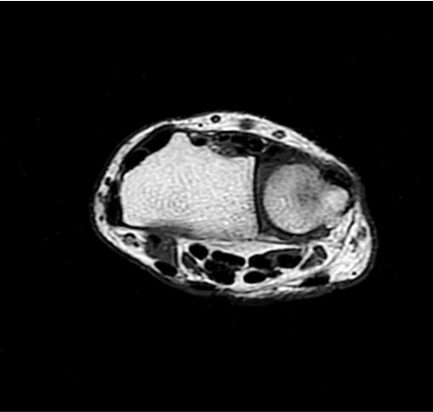

Conventional

384 x 256 (4 NEX)

3:00 minIAI (Innovative AI)

384 x 256 (2 NEX)

1:29 minscan time reduced up to 50%